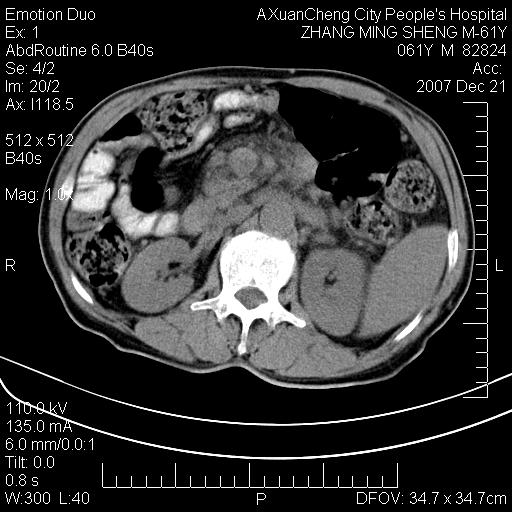

标题: CT11031:M61Y,胰腺占位 [打印本页]

标题: CT11031:M61Y,胰腺占位

大家侃侃门静脉和胆管系统怎么回事,肝内转移?

1,肝硬化,脾大.

2,肝内多发结节状低密度占位,伴门脉及肠系膜上v栓子形成.考虑a;门脉及肠系膜上v血栓后肝改变.b;弥漫型肝癌伴门脉及肠系膜癌栓.

肝硬化,门脉高压,脾肿大;弥漫性肝癌,肝内、门脉、腹膜后淋巴结转移,肝内外胆管扩张,胰头区占位,建议mr检查

胰腺癌伴肝内转移;门脉、肠系膜上v癌栓形成。

考虑为:胰腺癌伴肝脏转移、腹膜后淋巴结转移,门静脉及肠系膜上静脉瘤栓形成。

胰体尾癌伴肝内转移,门静脉及肠系膜上静脉瘤栓形成.